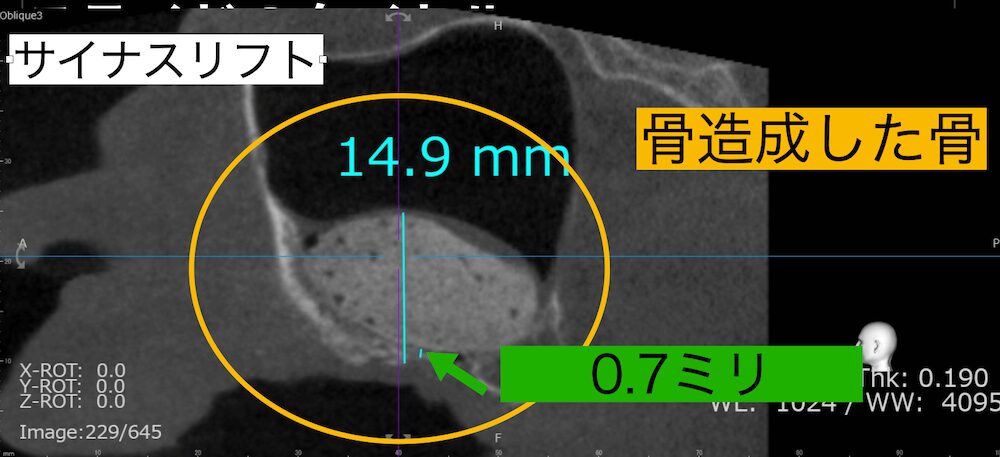

左上の奥歯の部分に0.6ミリほどしか骨がありませんでした。そこへ10ミリ近くのインプラントを埋入するには骨造成が必要となります。サイナスリフトを行い上顎洞へ骨造成を行いました。

上顎洞に12ミリほどの高さまで骨造成を行いました。

これにより十分な骨量が確保できたため、無事インプラントを埋入することができました。